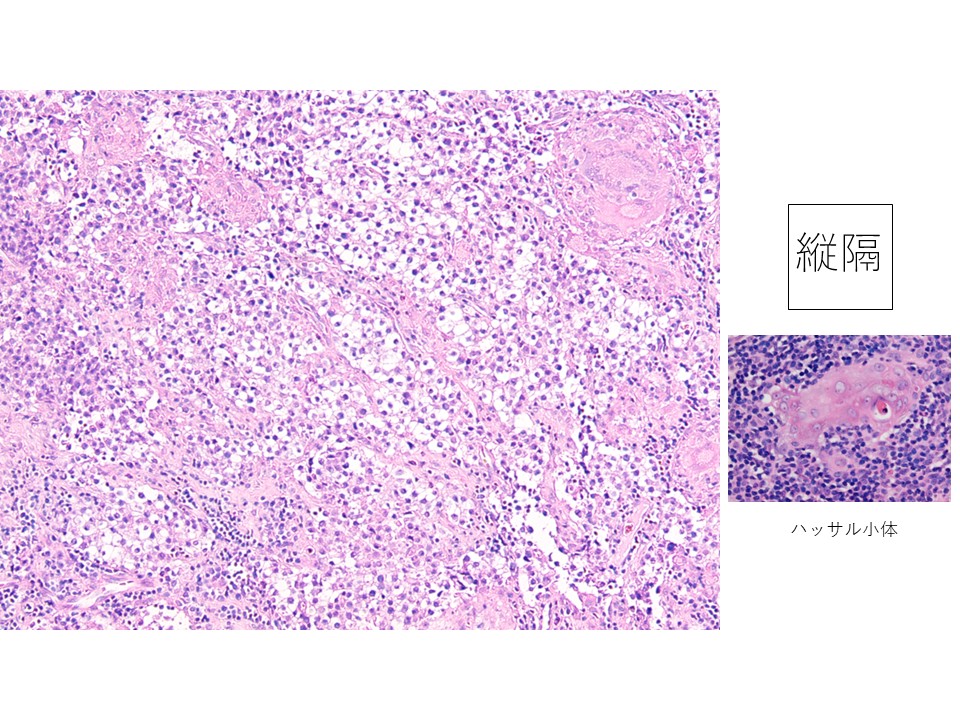

縦隔腫瘍スタンプ:背景にリンパ球を認める。結合性は弱く小シート状または孤立散在性、細胞質はライトグリーンに淡染し、核は円形から類円形で核縁の肥厚は無い。明瞭な1個から2個の核小体を認める。

縦隔組織:核小体が明瞭な腫瘍細胞とリンパ球のtwo cell patternを示す。免疫染色の結果c-kit陽性で、セミノーマと診断。その他の胚細胞腫瘍の存在は証明できなかった。